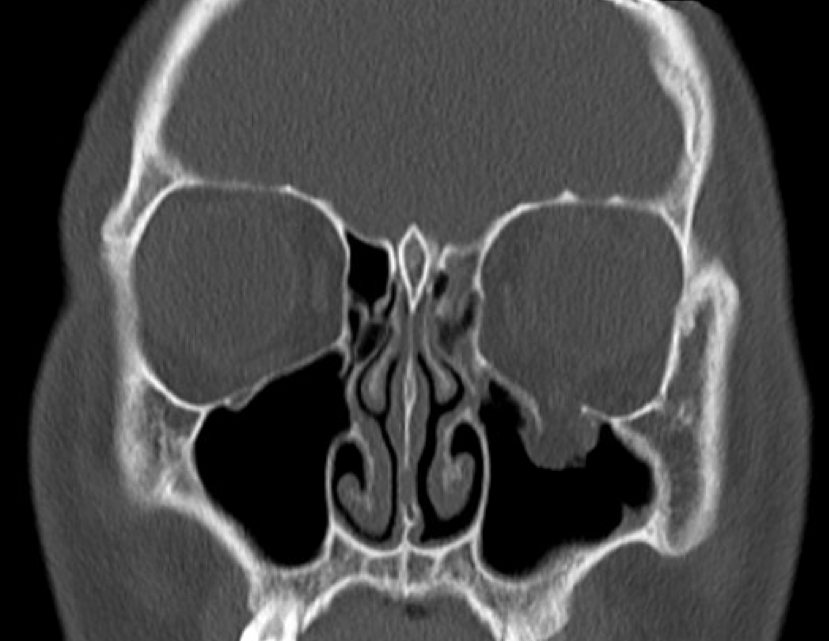

The floor of the orbit is made up of maxilla and zygomatic bone. Fracture in this part of the orbit is most common among all the blowout fractures of orbit. Patient with orbital floor fracture may present with eccyhmosis and periorbital edema. Proptosis and altered sensation on the face may be present. Reference: http://brownemblog.com/blog-1/2018/12/31/orbital-floor-blowout-fracture Image via: http://brownemblog.com/blog-1/2018/12/31/orbital-floor-blowout-fracture